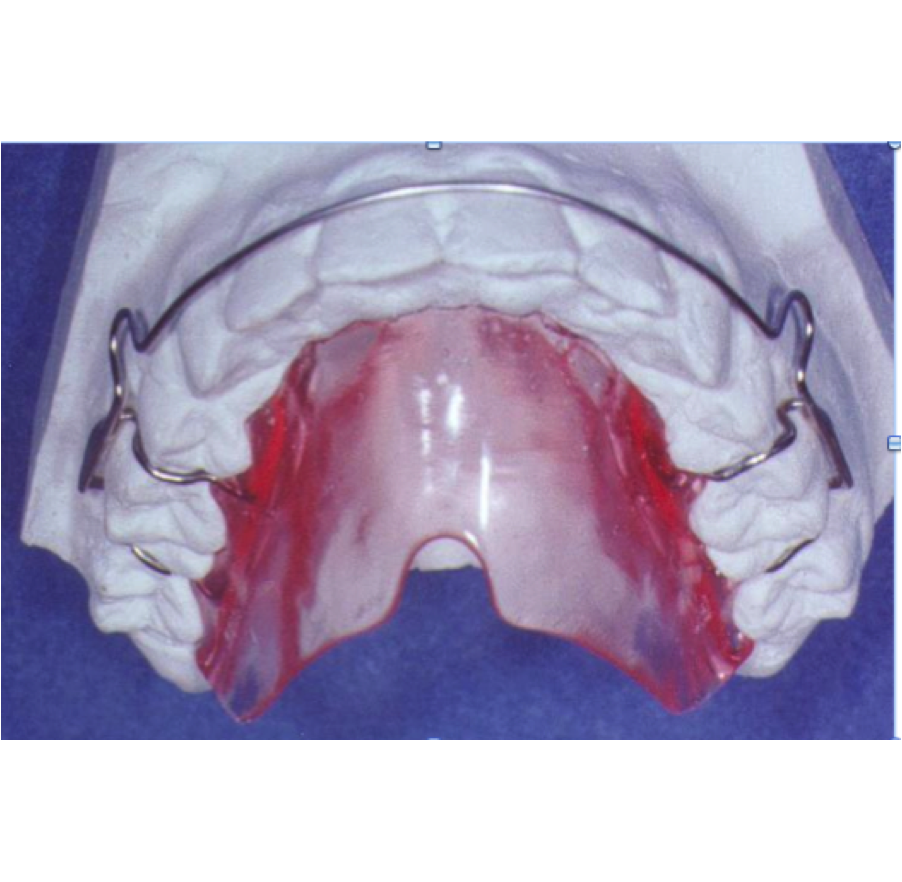

Les appareils amovibles, que le patient peut retirer. Les appareils ont divers ressorts et vérins, positionneurs.